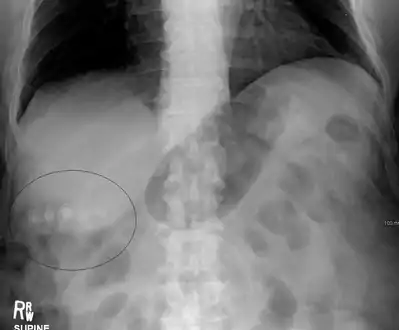

Gallstones as seen on plain X-ray Gallstones as seen on plain X-ray

Diagnosis is typically confirmed by abdominal ultrasound. Other imaging techniques used are ERCP and MRCP. Gallstone complications may be detected on blood tests.[2]

On abdominal ultrasound, sinking gallstones usually have posterior acoustic shadowing. In floating gallstones, reverberation echoes (or comet-tail artifact) is seen instead in a clinical condition called adenomyomatosis. Another sign is wall-echo-shadow (WES) triad (or double-arc shadow) which is also characteristic of gallstones.[36]